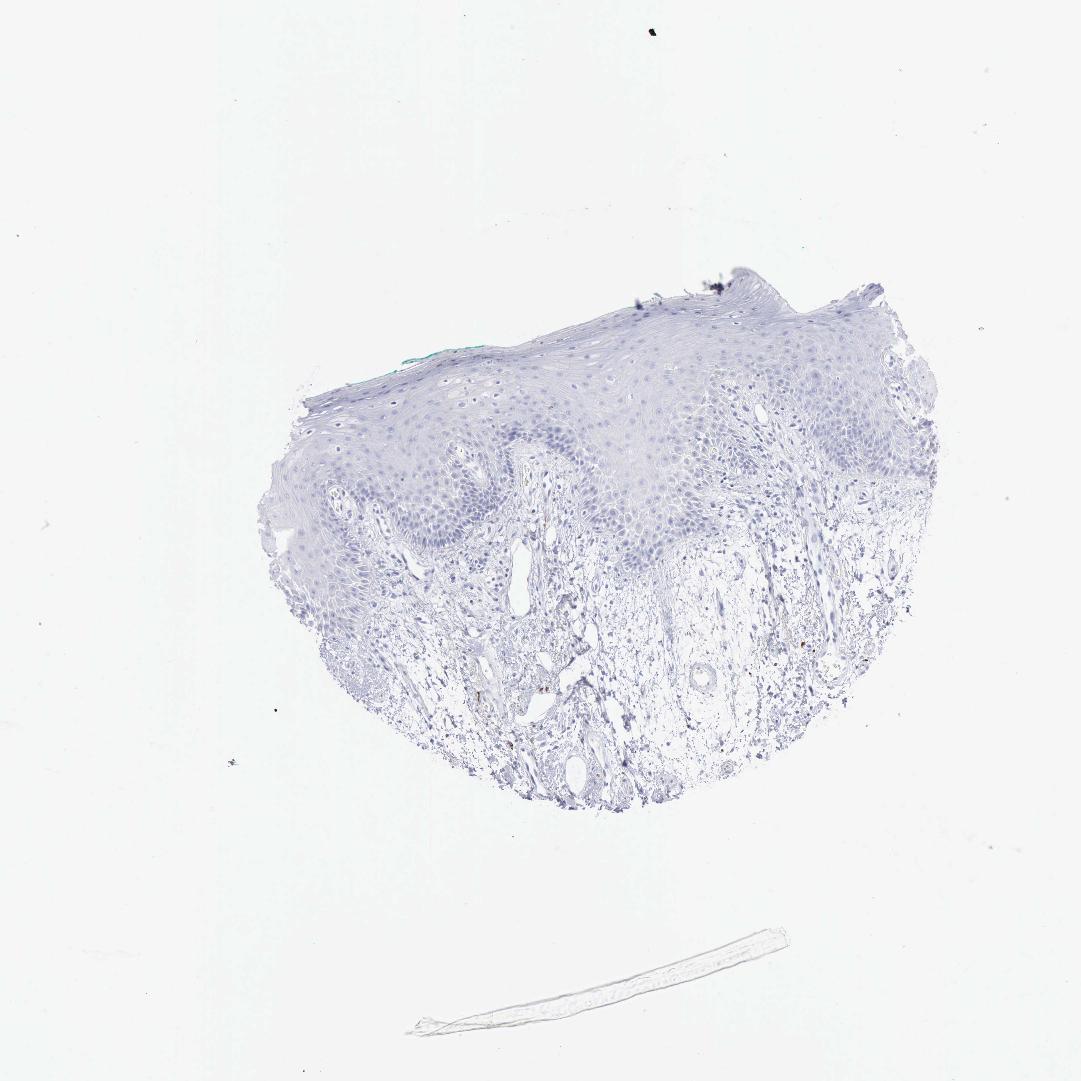

TISSUE PRIMARY DATA ORAL MUCOSA Show tissue menu

Oral mucosa

ORAL MUCOSA - Antibody stainingi

Antibody staining in the annotated cell types in the current human tissue is reported as not detected, low, medium, or high, based on conventional immunohistochemistry profiling in selected tissues. This score is based on the combination of the staining intensity and fraction of stained cells.

Each image is clickable and will lead to virtual microscopy that enables deeper exploration of all samples and also displays staining intensity scores, fraction scores and subcellular localization as well as patient and tissue information for each sample.

Antibody HPA039835Antibody CAB000142Antibody CAB018071

Squamous epithelial cells Not detectedNot detectedNot detected